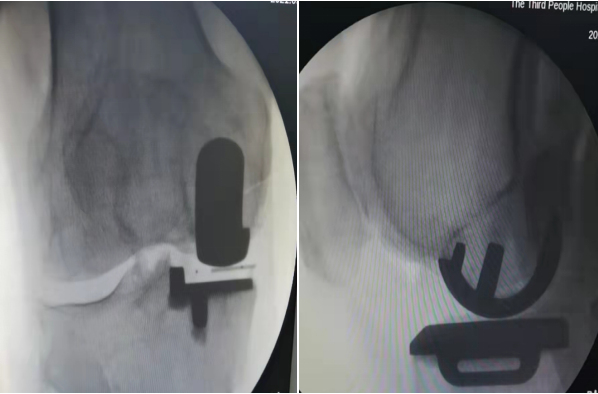

2021年9月4日,我院外一科医师团队在雷寿斌副院长的带领下,成功完成了我院首例膝关节单髁置换术,患者术后关节活动不受影响,效果显著。手术的成功,标志着我院膝关节置换术向微创化、个体化、精准化方向又迈进了一大步。

单髁置换手术是近年来国际上先进的微创手术之一,相较于传统的全膝关节置换术更加微创,且能最大限度地保留患者正常的关节部分,对患者的损伤更小,术后疗效更佳,是骨性关节炎患者的又一大福音。